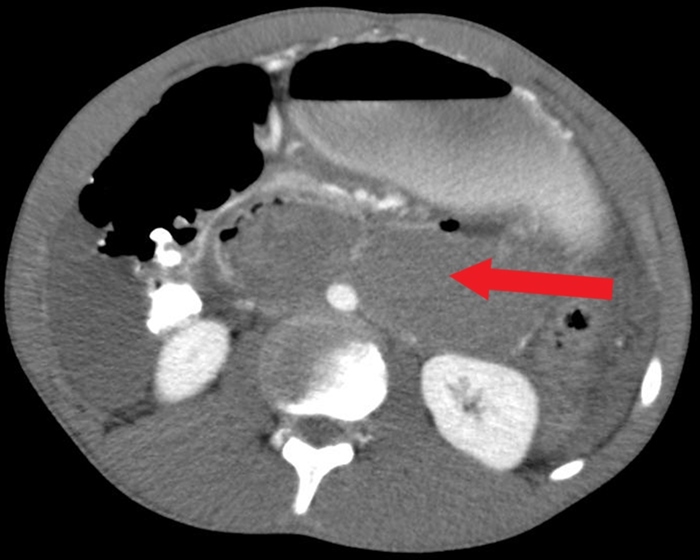

CT scan of the abdomen gives detailed information about the pathology and source of hemorrhage (if present). It may also assist in planning of operative intervention.

Renal laceration may present with hematuria, but urinary retention would be unusual. Patients with this injury usually have flank pain and hemorrhage into the retroperitoneal space.

Renal injuries can be usually managed conservatively. Only severe injuries, such as vascular injury or parenchymal laceration extending through the renal cortex, medulla, and collecting system, warrants surgery.